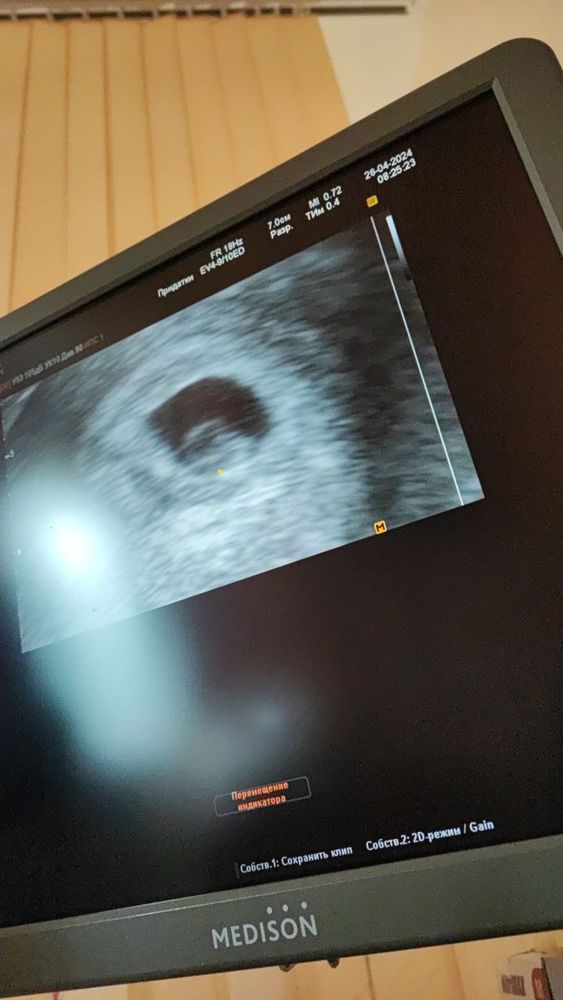

Наше первое узи, срок 6+3 (7+3)

Учитывая, что у меня последние М были 05.03, а овуляция поздняя на 22 ДЦ, то думаю срок 6-7 недель соответсвует. По М у меня срок 7+3, если считать от О назад 14 дней, то 6+3. По узи сказали полных 6 недель, написали 6-7 недель.

Длина туловища эмбриона - это я так понимаю ктр, смешно написали))

Наиля , дааа, при чем не смотря на позднюю овуляции, практически по сроку не отстает. Сначала немного парилась из-за размера СВД , что он 16 мм, а эмбриончик аж 6 мм. но и врач и узист сказали, что всё хорошо